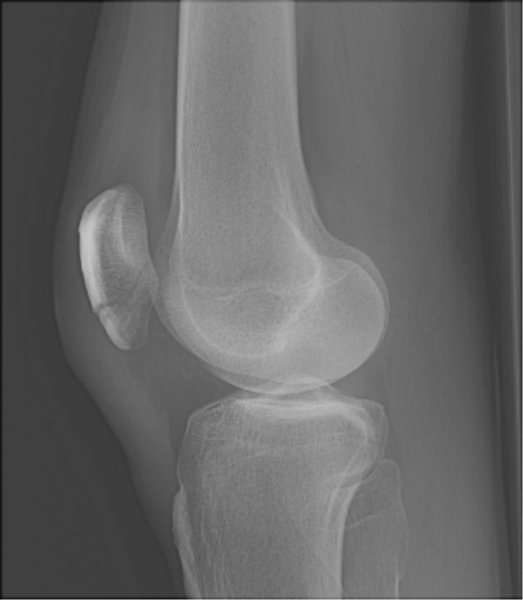

Return to Patellar Fracture